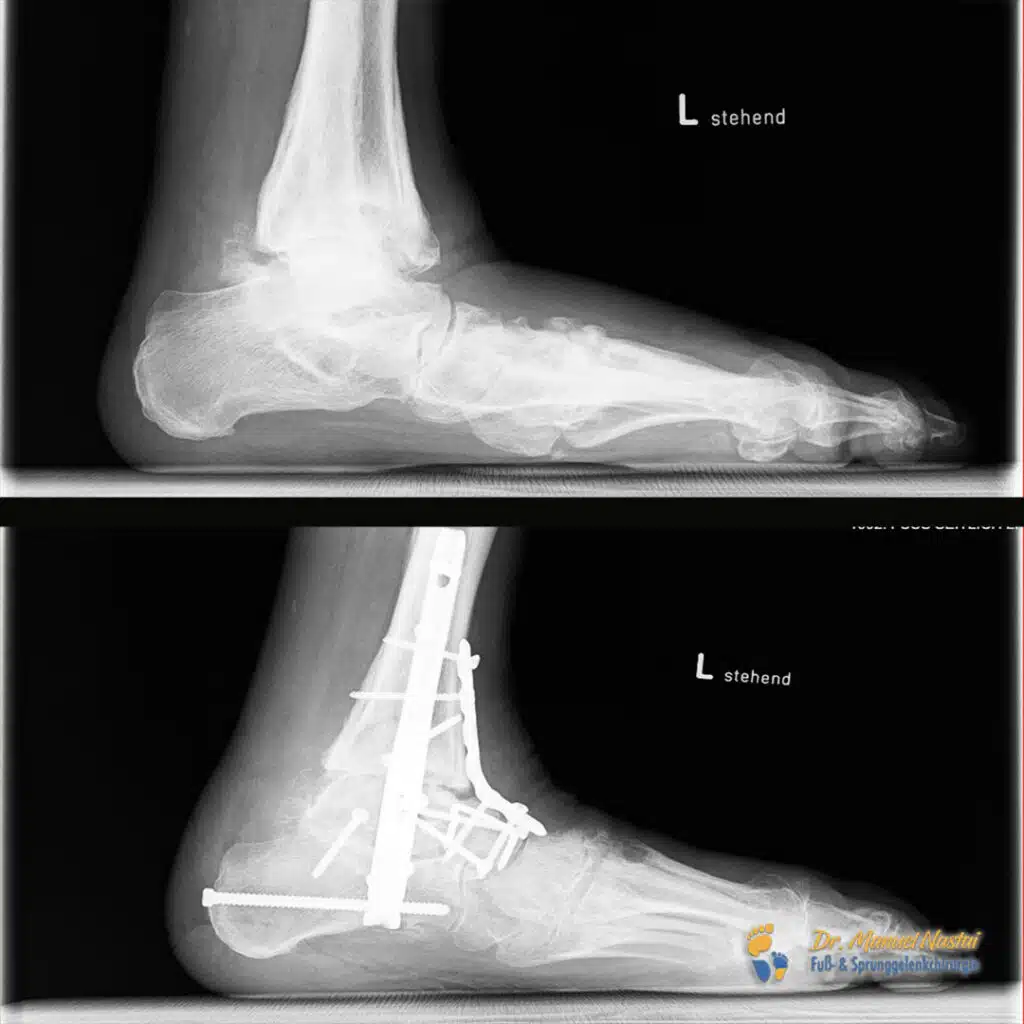

Komplexe Rückfußversteifung mit Achskorrektur: oberes Sprunggelenk (OSG), unteres Sprunggelenk (USG) und die Chopart’sche Gelenkreihe wurden in korrigierter Stellung arthrodesiert.

Implantate & Technik:

Einsatz eines retrograden Sprunggelenksnagels (plantar/transkalkaneal bis in die Tibia) mit proximaler und distaler Verriegelung. Der Nagel ermöglichte eine potente axiale Kompression der Arthrodese-Flächen für die knöcherne Durchbauung. Zusätzlich wurde die tarsale/Chopart-Reihe aufgerichtet und mit Schrauben, Klammern und einer winkelstabilen Platte fixiert.

6 Wochen postoperativ: Gute Korrektur klinisch und radiologisch; reizlose Wunden, Restschwellung noch sichtbar.

3 Monate postoperativ: Die Patientin ist wieder selbstständig und sicher in orthopädischen Maßschuhen mobil; Gehen über alltagsübliche Distanzen mit regelrechter Abrollbewegung ist schmerzarm möglich. Die Wundheilung verlief primär und komplikationslos, ohne Infektzeichen; die Narben sind reizlos und weich. Im Vergleich zu präoperativ zeigt sich eine vollständige Wiederherstellung der Fußstatik mit neutral zentrierter/gerader Fersenachse und rekonstruiertem Längsgewölbe. Klinisch findet sich eine gleichmäßige plantare Lastverteilung ohne druckbedingte Hotspots; rezidivierende Läsionen oder Hyperkeratosen im Mittelfußbereich traten nicht mehr auf.